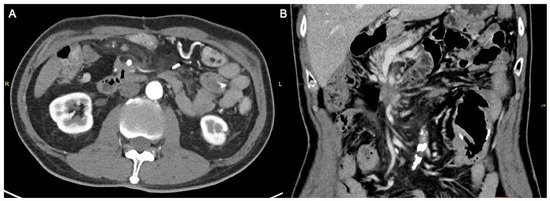

Following the combination therapy, the pancreatic tumor showed significant reduction in size (Figure 6A,B), with patient survival at 53 months post-diagnosis at the time of writing.

Figure 6.

Axial (A) and coronal (B) computed tomography images demonstrating the remnant pancreatic tumor, now smaller in size and extent, measuring approximately 2.3 cm.